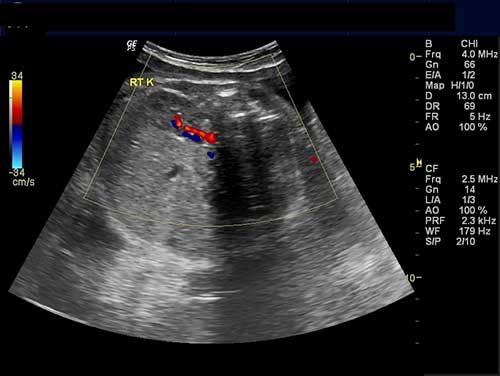

Okay, so the last choice isn't really an option, but you get the picture when it comes to the variety of ultrasound imaging.

Challenge your anatomy knowledge; what body part is this 3-D image showing?